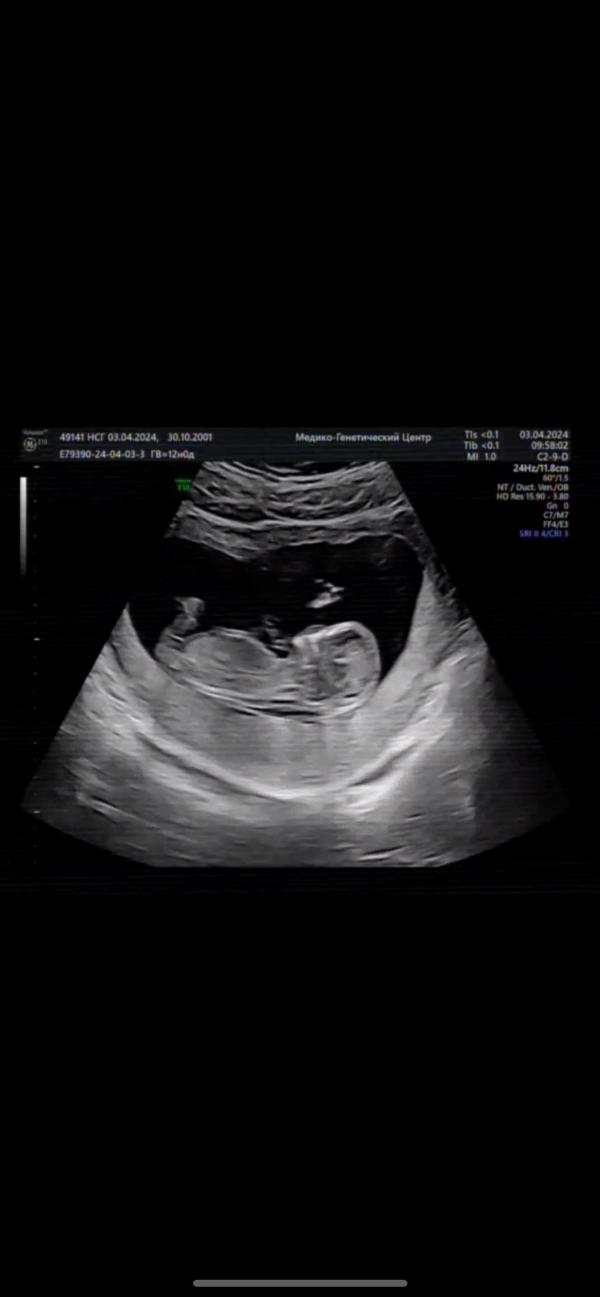

Скрининг показал - у нас будет дочка! Очень счастливы!

post image 2

Любимое фото. Сегодня был первый скрининг.

У нас по воле Всевышнего будет дочь🩷

Мы очень счастливы! 💕

03.04.2024